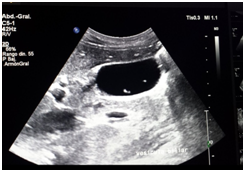

Male patient of 37years of age , white race, resident in Habana del Este municipality of Havana province, with previous health history that comes to consultation for presenting prolonged febrile syndrome with 56days of evolution, febrile peaks of 38‒39 degrees, accompanied by chills and decay. Urinary sepsis was determined as initial diagnosis so antimicrobial treatment was imposed for 10 days. There is no improvement in the clinical picture and the febrile symptoms persist. The patient is admitted to the hospital service of the Central Hospital in Havana. On physical examination, painful abdomen on palpation in the right hypochondrium and epigastrium without other alterations Laboratory tests are performed or presenting Haemoglobin: 12gl, Leucogram which yields an Eosonophilia of 66% and an Erythrosedimentation: 67. Serial blood cultures and urine cultures they were negative. Likewise, the serology was negative. Within imaging studies abdominal ultrasound reporting hepatomegaly that exceeds be 2 cm costal margin with the presence of a hypo echoic image with nodular, peripheral tendency without flow Doppler level right lobe study (Figure 1) interpreting c indicated omo pyogenic liver abscess therefore imposes treatment with antimicrobial therapy (Metronidazol EV) (Figure 1). Ultrasound: nodular, hypoechoechoic, peripheral, non‒vascularised image at the level of the right lobe of the liver clinically the patient improved his general condition, but he kept the febrile syndrome accompanied by diffuse abdominal pain. By keeping the same ultrasound image last month of treatment study it was conducted by T omografía who reported abdominal the presence of density areas of irregular appearance, in the right lobe of the liver in segments VII and VIII and endovenous study showed lesions with poor contrast capitation both Portal and late phase (Figure 2). Computed tomography with intravenous contrast: hypo dense areas of irregular appearance at the level of segments VII and VIII of the liver with poor contrast uptake Ultrasound images suggested the diagnosis of parasitosis Fasciola hepatica but also by positron raised the differential diagnosis of Focal nodular hyperplasia at que sugi river echo directed FNA that reported cytological Negative of neoplastic cells and inflammatory infiltrate with abundant eosinophils. Given this possible diagnosis, endoscopy was performed, which reported alkaline pangastropathy with a duodenal swab for negative parasitological study. Conical crown was made on several occasions resulting negative and biliary drainage was indicated to be not useful for diagnosis. In view of Clinical and Imaging suspicion of Fasciola hepatica, it was decided to perform a weekly evaluative ultrasound for 4 more weeks, observing at the end of the fourth week echogenic images, elongated with movements inside the gallbladder and an echogenic image without acoustic shadow in the canal. Coledochus suggesting the diagnostic imaging of adult Fasciola parasites in the bile ducts (Figure 3). Evolutionary ultrasound: echogenic images, free, with movement at the level of the gallbladder. The patient was referred to the Institute of Tropical Medicine (IPK) where the diagnosis was verified, imposing treatment with a single oral dose of Triclabendazole with excellent therapeutic response.

Figure 1 Ultrasound.

In hepatic fascioliasis, hypo echoic, anfractuous, well‒defined focal lesions of variable size can be observed, with a tendency to accentuate in 96% of cases (similar to the case reported), although variable echo genicity is also described . However, it is not always possible to visualize the paths that give it the characteristic stamp, so its role in acute Fasciolosis is less. The presence of per portal adenopathies is also described in 74% of cases, although this finding is nonspecific and is present in acute and chronic hepatitis, abdominal neoplasm’s, abdominal tuberculosis and sclerosing cholangitis, among other pathologies.13,14 In Biliary Fascioliasis, the role of ultrasound is greater, given that it is able to confirm parietal thickening of the common bile duct with moderate dilation , although this finding is also seen in pathologies such as sclerosing cholangitis and AIDS cholangitis . More specific is the observation of mobile structures in the gallbladder and / or common bile duct, representing the adult form of Fasciola,14,15 a finding found in the reference patient.